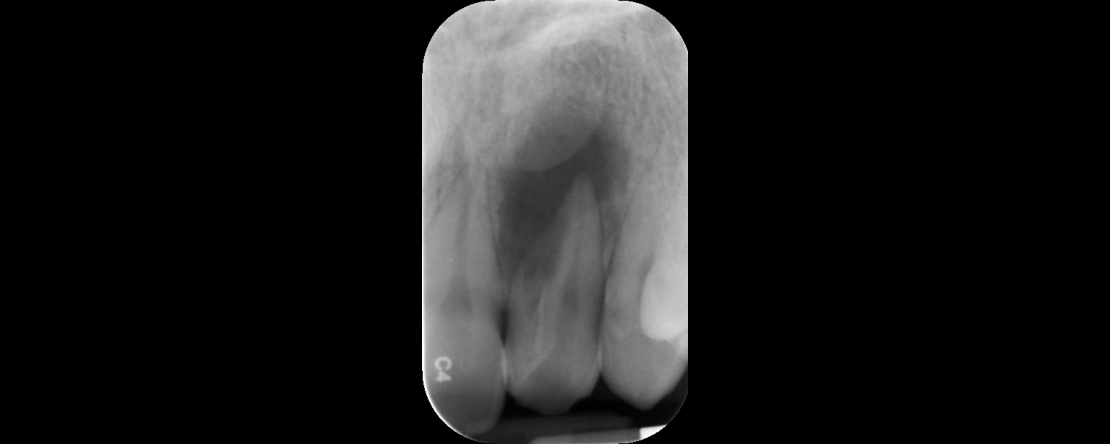

Num mundo em que já tudo parece ter sido criado para instrumentar, desinfetar e obturar o sistema de canais radiculares, como será possível que a taxa de sobrevida e sucesso endodôntico ainda não seja 100%? Será exequível que o sistema de canais radiculares não esteja adequadamente desinfetado? Ou será que o problema reside no exterior deste mesmo sistema?

• Perceber o potencial papel da infeção cruzada no sucesso do tratamento endodôntico.

• Discutir técnicas e materiais de desinfeção do campo operatório e sistema de canais radiculares.

• Debater certos aspetos da persistência microbiana e o seu envolvimento no fracasso endodôntico.

• Rever técnicas contemporâneas de desinfeção do sistema de canais radiculares.